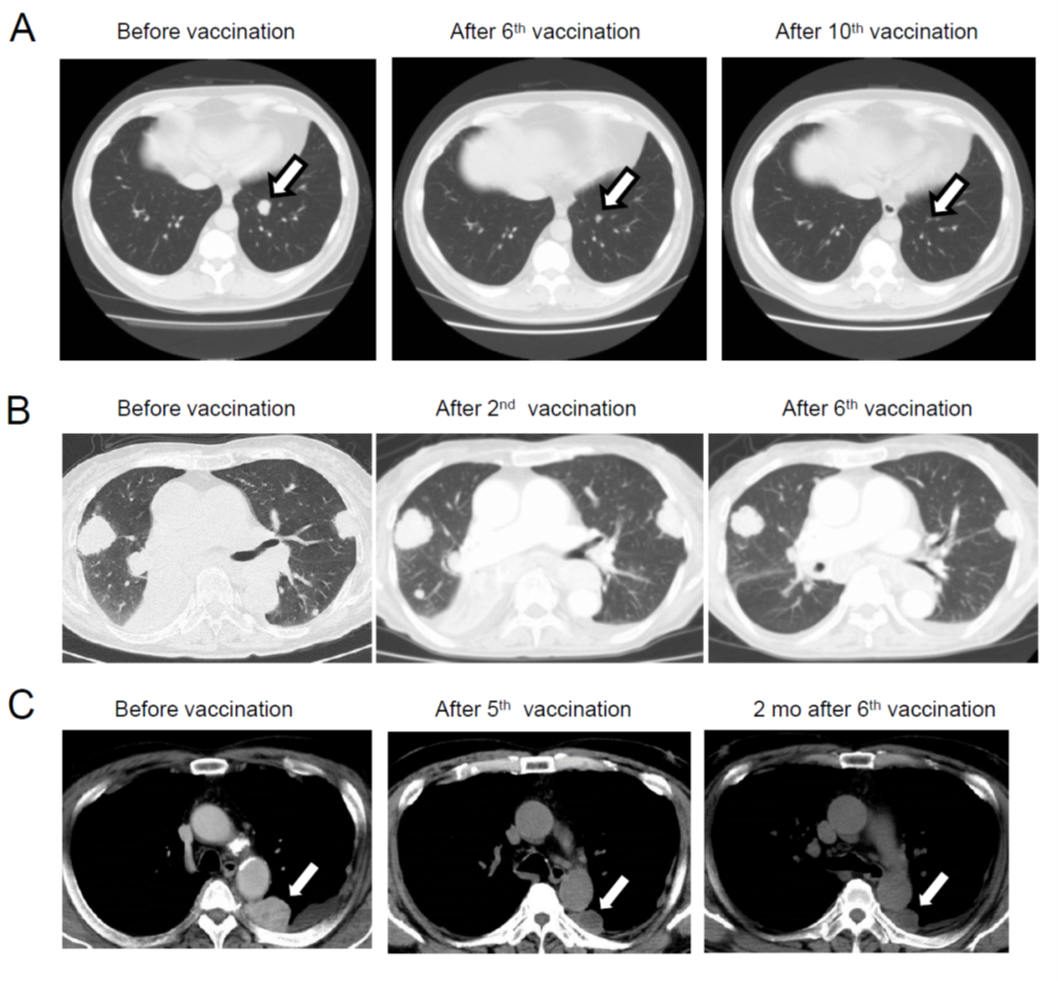

3.3がんワクチン

NY-ESO-1ペプチドワクチン

岡山大学中山睿一教授・大阪大学和田尚教授、川崎医科大学岡三喜男との共同研究でNY-ESO-1抗原を発現する進行・再発、食道・胃・肺および卵巣癌患者(手術不能な病期分類III、IV期、及び術後再発症例)に対してNY-ESO-1fペプチドのOK-432およびモンタナイド(Montanide)併用皮下反復投与における安全性について、有害事象の種類、程度、頻度を評価する臨床試験を行いました。東大病院では、呼吸器外科中島淳教授、胃食道外科瀬戸泰之教授とともに多くの患者さんにワクチンを投与しました。試験を通じて、NY-ESO-1抗原特異的免疫反応誘導効果および抗腫瘍効果について詳細に評価誌多くの論文を発表しました。

従来のペプチドワクチンでは、ワクチンに反応したT細胞は、ぺプチドに反応するが、がん細胞に反応できない弱点がありました。そこで、私たちは、ロングペプチドワクチンを臨床試験に導入しました。

治療経過を詳細に観察し、ワクチンによって誘導されたNY-ESO-1特異的免疫応答の体内動態を経時的に解析し、抗腫瘍効果との関係を検討しました。

樹状細胞ワクチン

従来のペプチドワクチンは、誘導されたT細胞が、皮下に投与された部位に残存するペプチドに対して反応し、exhaustの状態に陥り、腫瘍内への抗原特異的T細胞浸潤は減弱するという弱点があった。一方、皮下に投与された樹状細胞は、リンパ節へ移動し、強い抗原特異的T細胞を誘導し、活性化されたエフェクター型のT細胞が腫瘍へ浸潤することから、より強力な抗腫瘍効果が誘導されると期待された。

我々は、マウスのモデルを用いて、ペプチドワクチンで誘導された抗原特異的T細胞と樹状細胞ワクチンで誘導されたこうげんとくてきT細胞のNGS解析を行い、分子レベルでの違いを評価した。樹状細胞で誘導した抗原特異的T細胞は、セントラルメモリー型の形質を持ち、増殖脳に優れたT細胞であった。

ペプチドワクチンによって誘導されたT細胞は、腫瘍内でPD-1・Tim-3を発現し、exhasutの状態に陥りやすいが、樹状細胞ワクチンで誘導された抗原特異的T細胞はPD-1・Tim-3の発現は3分の1程度に抑えられており、腫瘍内でも活性が持続することが期待された。

腎細胞がんに対する樹状細胞ワクチン治療

腫瘍特異的T細胞は、腫瘍特異的遺伝子変異産物である変異アミノ酸を含んだタンパク、ネオアンチゲンに反応することが知られていた。当時は、まだ個々の患者の遺伝子変異を同定し、一人一人の患者に合わせてがんワクチンを調製することは不可能であった。そこで、樹状細胞ワクチンで用いる抗原として、我々は腫瘍溶解物(ライセ―ト)に着目した。

腫瘍内には、当然ネオアンチゲンが含まれており、腫瘍溶解物には複数のネオアンチゲンが含まれている可能性が期待された。そこで、東大病院泌尿器科(当時の本間之男教授、久米春喜准教授(現教授)榎本裕講師(現在三井記念病院)、中川徹講師(現在の帝京大学医学部教授)とともに、腎摘出術を受ける転移性腎がん患者に対して、樹状細胞ワクチンの臨床試験を実施した。転移性腎がん患者は、腎摘出術後の転移巣の治療に分子標的薬のスニチニブの投与を受けることが標準治療として確立していた。スニチニブは、抑制性T細胞(Treg)やMDSCなどの抑制性細胞を減少させることから、樹状細胞ワクチンとの併用で、相乗効果・相加効果が期待された。

- 治療効果

次世代シーケンサー(NGS)により、個々の患者の腫瘍において、遺伝子変異を同定しネオアンチゲンが予測できるようになったことから、今後はネオアンチゲンを用いた樹状細胞ワクチン治療を開発していきたい。また、免疫チェックポイント阻害剤との併用や、TCR-T細胞治療などの併用など、最新の免疫制御技術を組み込んで、より効果的ながん免疫治療の開発に貢献したい。